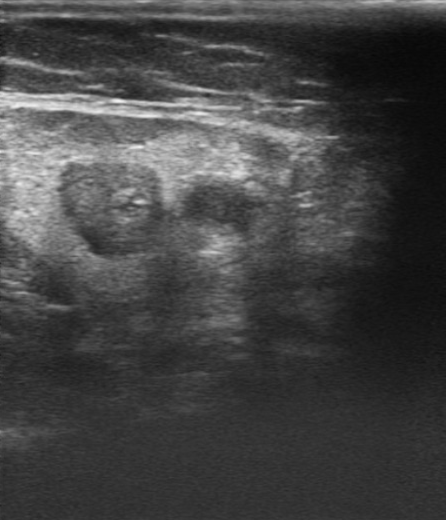

Ecografía de miembro inferior izquierdo: contenido hiperecogénico en todo el trayecto de la vena safena interna, no compresible. Sistema venoso profundo permeable sin datos de TVP (Imagen 2,3,4).